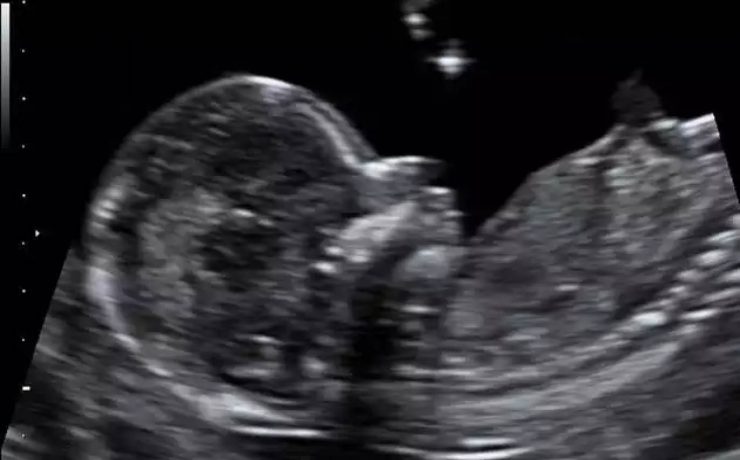

Alteraciones segundo trimestre de gestación.

Objetivo determinar la asociación entre ausencia e hipoplasia de hueso nasal fetal y alteraciones estructurales y o cromosómicas en el neonato, en la población en general en el ultrasonido del segundo trimestre. La gran mayoría de malformaciones congénitas no son prevenibles ya que constituyen accidentes